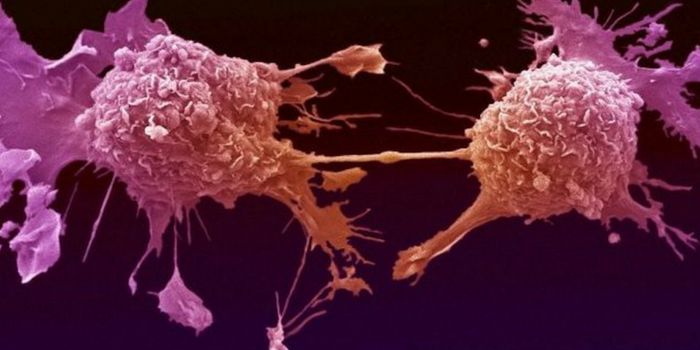

AUG 11, 2019Cell & Molecular BiologyCancer is most deadly when it metastasizes, which can happen after tumor-removal surgery. It's a serious challenge for m ...

APR 17, 2016CancerVirtually every type of cancer has metastatic potential – that is, the tumor cells can leave its original site and ...